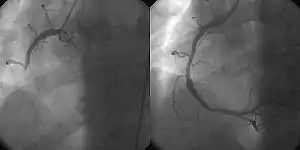

Coronary angiography and angioplasty in acute myocardial infarction (left: Right Coronary Artery [RCA] closed, right: successfully dilated)

The main advantages of using the interventional cardiology or radiology approach are the avoidance of the scars and pain, and long post-operative recovery. Additionally, interventional cardiology procedure of primary angioplasty is now the gold standard of care for an acute myocardial infarction. It involves the extraction of clots from occluded coronary arteries and deployment of stents and balloons through a small hole made in a major artery, which has given it the name "pin-hole surgery" (as opposed to "key-hole surgery").

the use of angioplasty for the treatment of obstruction of coronary arteries as a result of coronary artery disease. A deflated balloon catheter is advanced into the obstructed artery and inflated to relieve the narrowing; certain devices such as coronary stents can be deployed to keep the blood vessel open. Various other procedures can also be performed at the same time. After a heart attack, it can be restricted to the culprit vessel (the one whose obstruction or thrombosis is suspected of causing the event) or complete revascularization; complete revascularization is more efficacious in terms of major adverse cardiac events and all-cause mortality.[4]